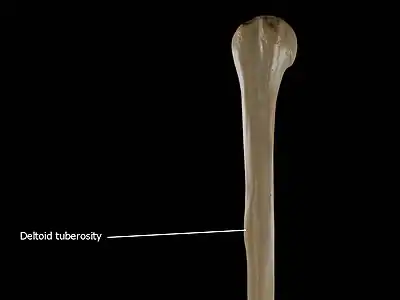

• Anterolateral surface: the area between the lateral border of the humerus to the line drawn as a continuation of the crest of the greater tubercle. The antero-lateral surface is directed lateralward above, where it is smooth, rounded, and covered by the deltoid muscle; forward and lateralward below, where it is slightly concave from above downward, and gives origin to part of the Brachialis. About the middle of this surface is a rough, rectangular elevation, the deltoid tuberosity for the insertion of the deltoid muscle; below this is the radial sulcus, directed obliquely from behind, forward, and downward, and transmitting the radial nerve and profunda artery.

The Deltoid tuberosity is a roughened surface on the lateral surface of the shaft of the Humerus and acts as the site of insertion of deltoideus muscle. The posterorsuperior part of the shaft has a crest, beginning just below the surgical neck of the humerus and extends till the superior tip of the deltoid tuberosity. This is where the lateral head of triceps brachii is attached.

Deltoid Tuberosity of the humerus